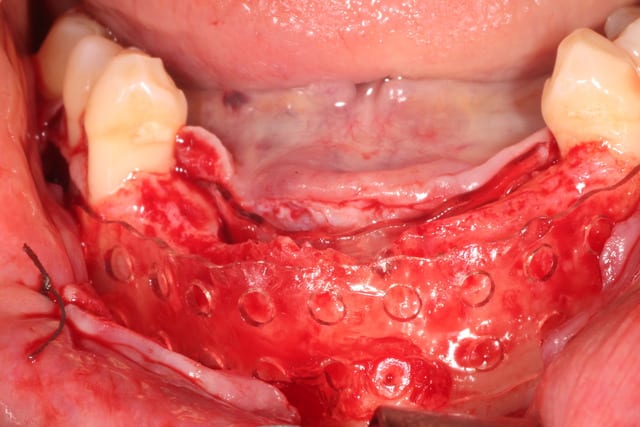

Bon, finalement, j'ai fait comme ça :

Oui, c'est bien en boxtechnique. J'ai fait une formation en avril dernier avec Andrea Menoni , initiateur de la technique en 2008. Je pense poursuivre à parme en octobre.

j'ai donc utilisé comme Maximini du MinerOss cortical-spongieux + autogene + prf + metro.

recouvert de prf, d'une membrane jason pericadium et de prf.

plaque resorb X , 0.8 mm, 11x126 mm : 235 €

5 pins : 350 €

MinerOss : 2.5 +1 cc : 360 €

Jason 4x3 : 180 €

Total : 1120 : oups, devis 1280 ! 3 heures !

Sur la video , il y a les deux techniques pour donner de la flexibilité au lambeau : technique Andréa avec le décolleur en lingual, et Maximini avec le Metzenbaum en vestibulaire.